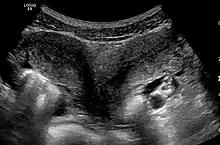

Ultrasound showing didelphys

Helpful techniques to investigate the uterine structure are transvaginal ultrasonography and sonohysterography, hysterosalpingography, MRI, and hysteroscopy. More recently 3-D ultrasonography has been advocated as an excellent non-invasive method to evaluate uterine malformations.[4]